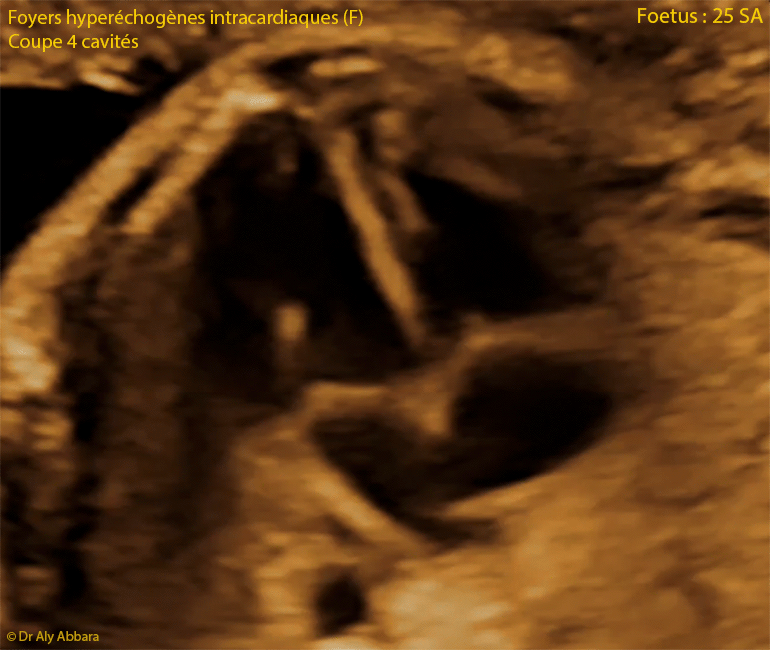

Foyer échogène intracardiaque multiple ou spots intraventriculaires : animation échographique - 25 SA

• Images échographiques montrant la présence, chez un fœtus de 25 SA, dans les deux cavités ventriculaires cardiaques, de multiple foyers hyperéchogènes (spots ou points lumineux - echogenic cardiac focus - ECF ; intracardiac echogenic focus - IEF)

• Le spot intraventriculaire est un foyer ou nodule hyperéchogène (d'une échogénicité égale à celle de l'os) ; il s'agit d'une calcification (minéralisation) du muscle papillaire et d'un pilier valvulaire ; sa taille est habituellement inférieure à 3 millimètre.

• Le spot intracardiaque peut être unique ou multiple.

• La présence de gros spots intra-cardiaques et bilatéralement, augmente le risque d'aneuploïdie fœtale comparé au risque en la présence d'un seul spot intracardiaque isolé.

• Dans le cas étudié dans cet article, le fœtus est âgé de 25 SA, ne présente aucune d'anomalie significative morphologique, biométrique avec naissance à terme sans trouble de développement.